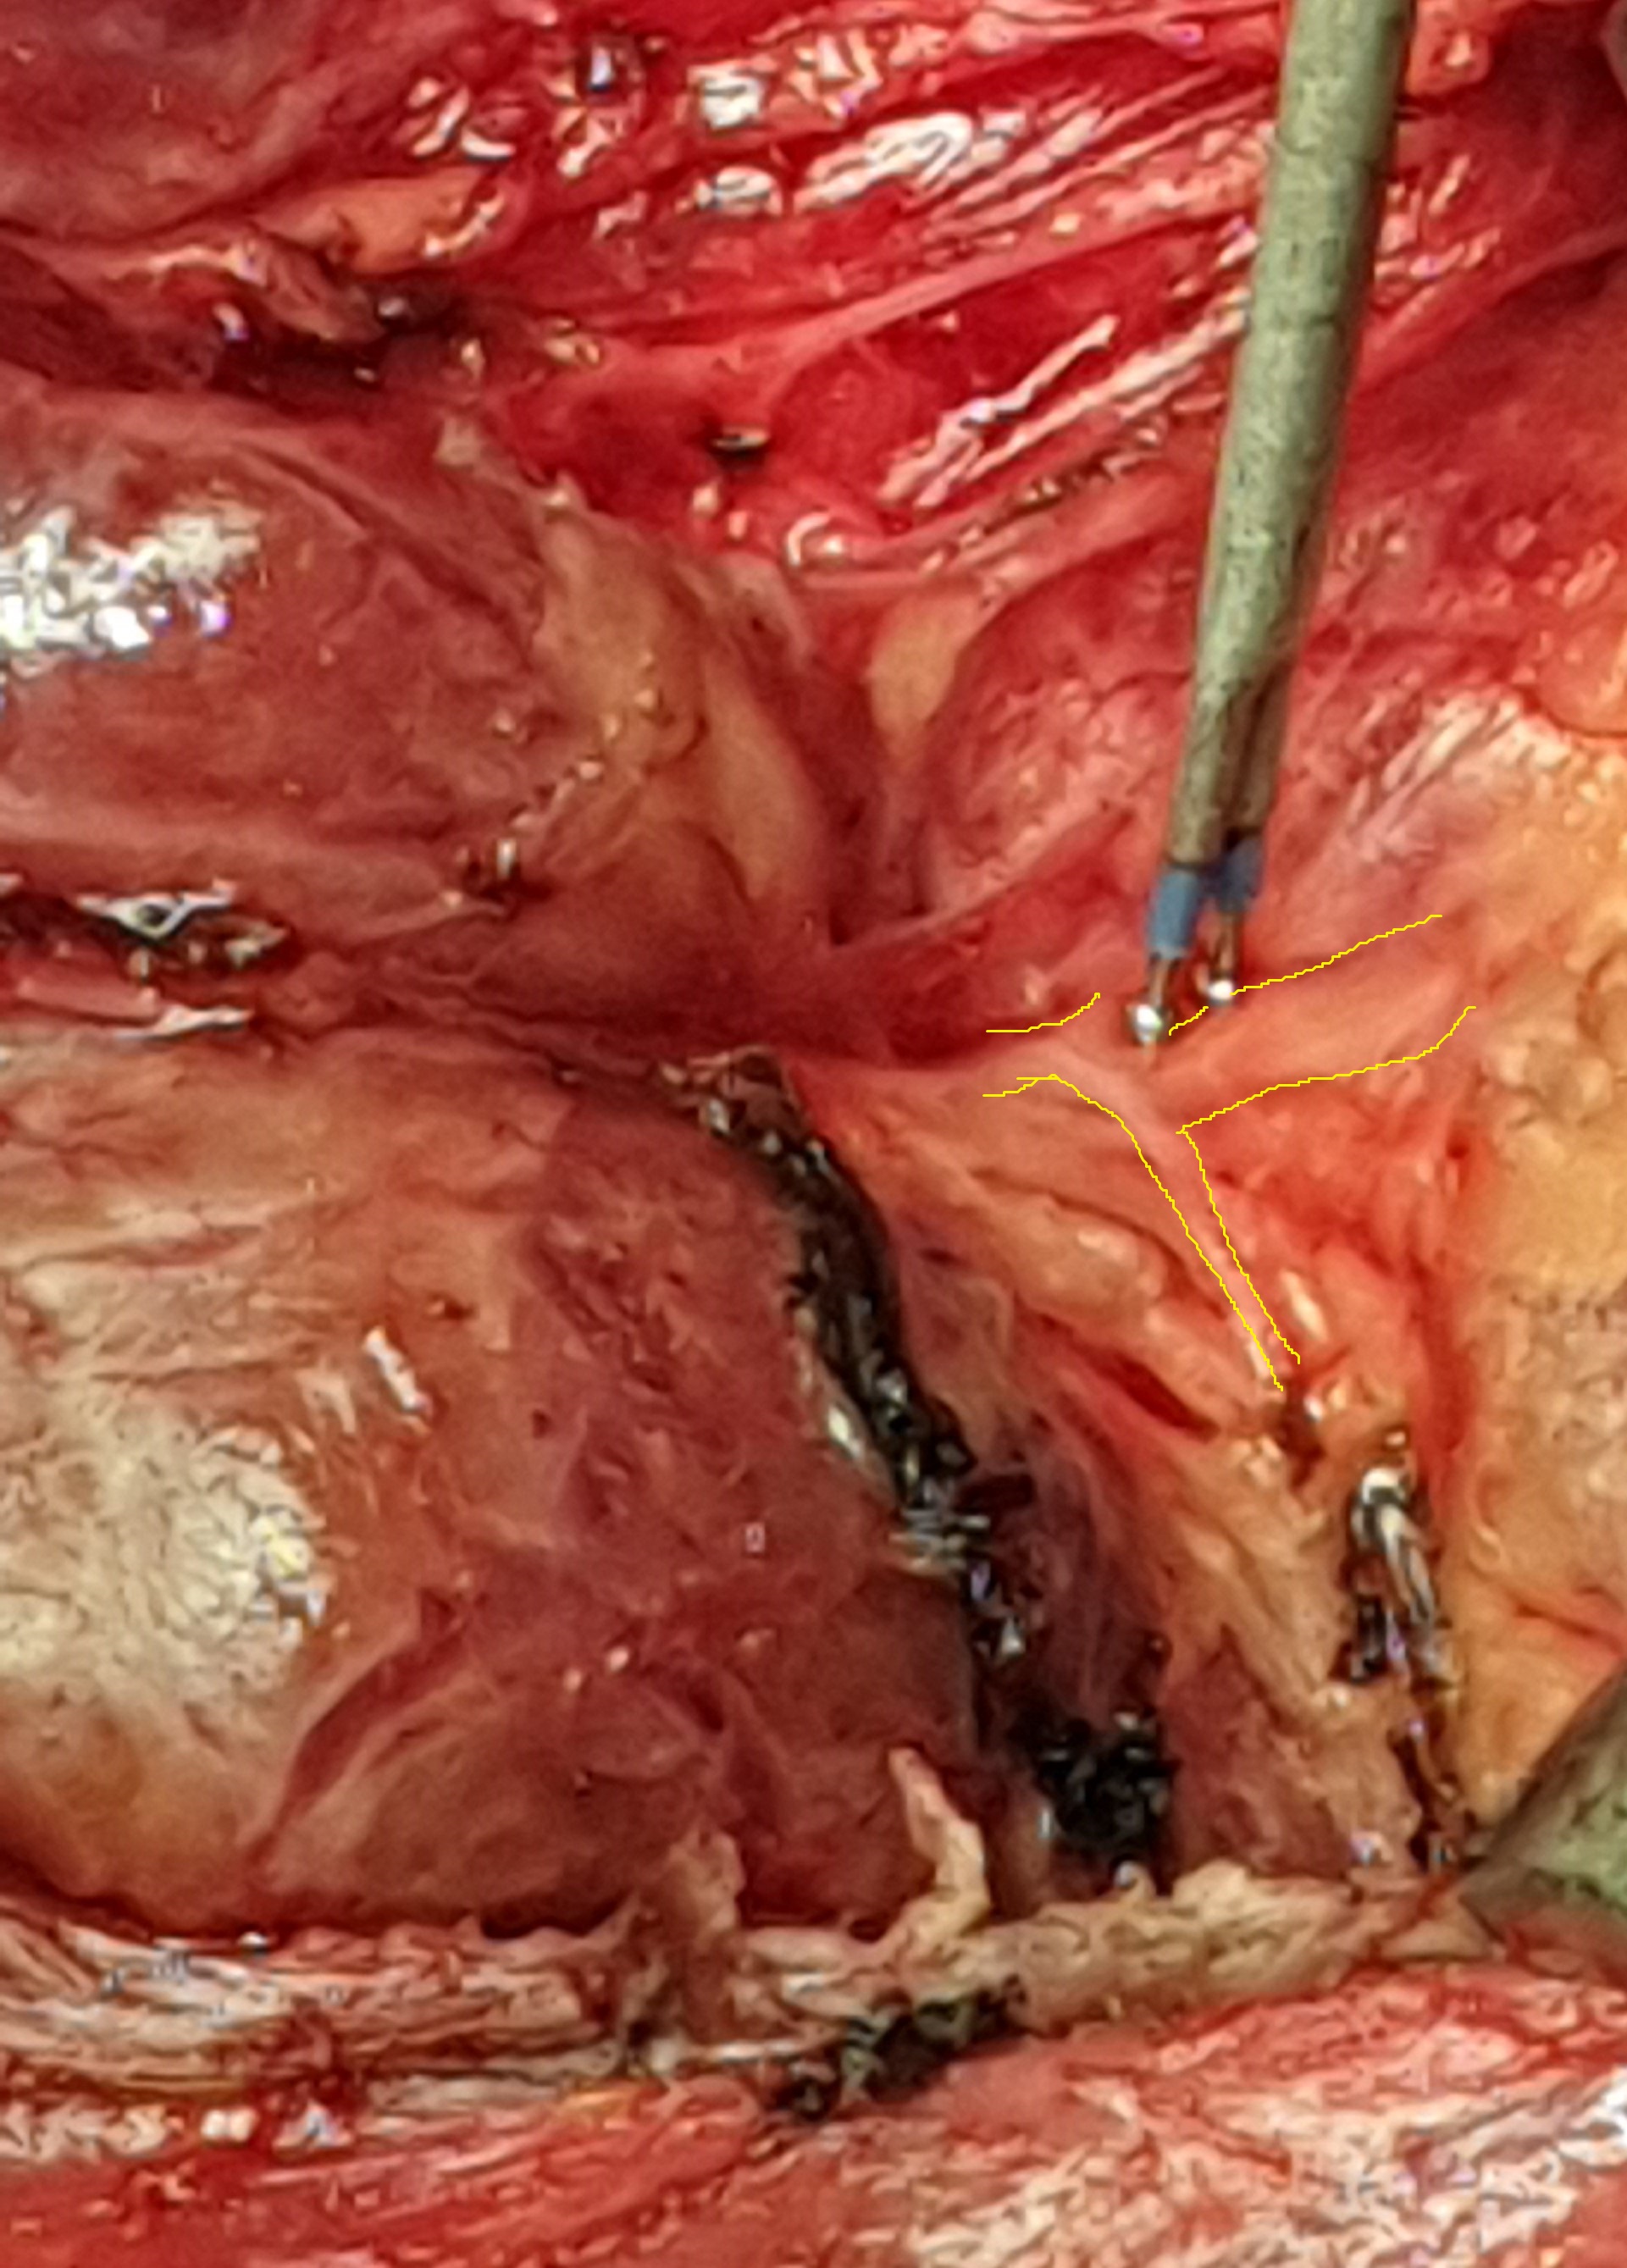

Green arrow — Right common carotid artery. Blue arrow — Right internal jugular vein. Purple arrow — Parathyroid adenoma. Yellow arrow — Right vagus nerve. Brown arrow — Trachea. Light brown arrow — Right recurrent laryngeal nerve (Courtesy Dr. V. Penopoulos)